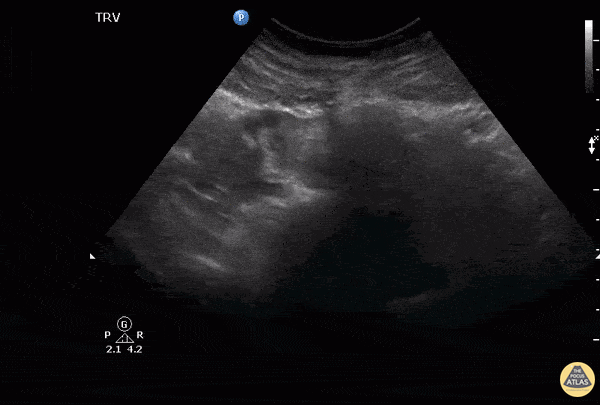

Notice to the left of the screen the presence of an adnexal mass separate to the ovaries which in this case indicates a right tubal ectopic pregnancy. Also noted here within the endometrium is an outer echogenic layer, middle hypoechoic layer and an inner hyperechoic stripe, which makes up the classic trilaminar pattern that is usually observable during the proliferative phase of menstruation. Image courtesy of Robert Jones DO, FACEP @RJonesSonoEM Director, Emergency Ultrasound; MetroHealth Medical Center; Professor, Case Western Reserve Medical School, Cleveland, OH View his original post here